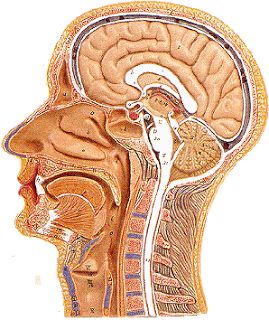

我们从头的外面开始。生物学研究有一点好,很多研究让人看了很有满足感,而脑本身有很多让人很满足的东西,其一就是人的头部其实跟个俄罗斯套娃一样。

我们的理解是,最外面是头发,下面是头皮,然后就是头部。其实不是这样的,头皮和头骨之间其实隔了19层东西。

而头骨下面,还有很多东西,然后才是大脑。

头骨下面,有三层膜包裹着大脑:

最外层的,叫硬脑膜,一层紧实、凹凸不平的防水层。硬脑膜紧贴着头骨。据说,大脑本身不能感知痛觉,但是硬脑膜可以,硬脑膜几乎和脸部的皮肤一样敏感。置于硬脑膜上的压力,或者硬脑膜的瘀伤是很多人头痛的原因。

硬脑膜下面是蛛网膜,是由一层皮和一层结缔组织组成的。我原以为我的脑是漂浮在一些头骨里面的一些液体里面的,然而其实头骨和脑之间唯一的空隙,其实就是蛛网膜的结缔组织间的孔。这些结缔组织使脑不会过多移动,当你的头撞到别的东西时能够起到减震的作用。这些空间里面充满了脊髓液,脊髓液的密度和水相近,所以大脑几乎是漂浮在其中的。

最后一层是软脑膜,一层柔软的和脑外部贴合在一起的皮。当你看到脑的照片的时候,很多时候脑都是被一层恶心的血管包裹住的,而这些血管其实并不是处在脑的表面,而是嵌在软脑膜里面。

下图是一个(应该是)猪头的三层膜的总览:

从左往右,分别是皮肤(粉色部分),然后两层头皮,然后头骨,接着才是硬脑膜、蛛网膜和软脑膜,最右边的是大脑。